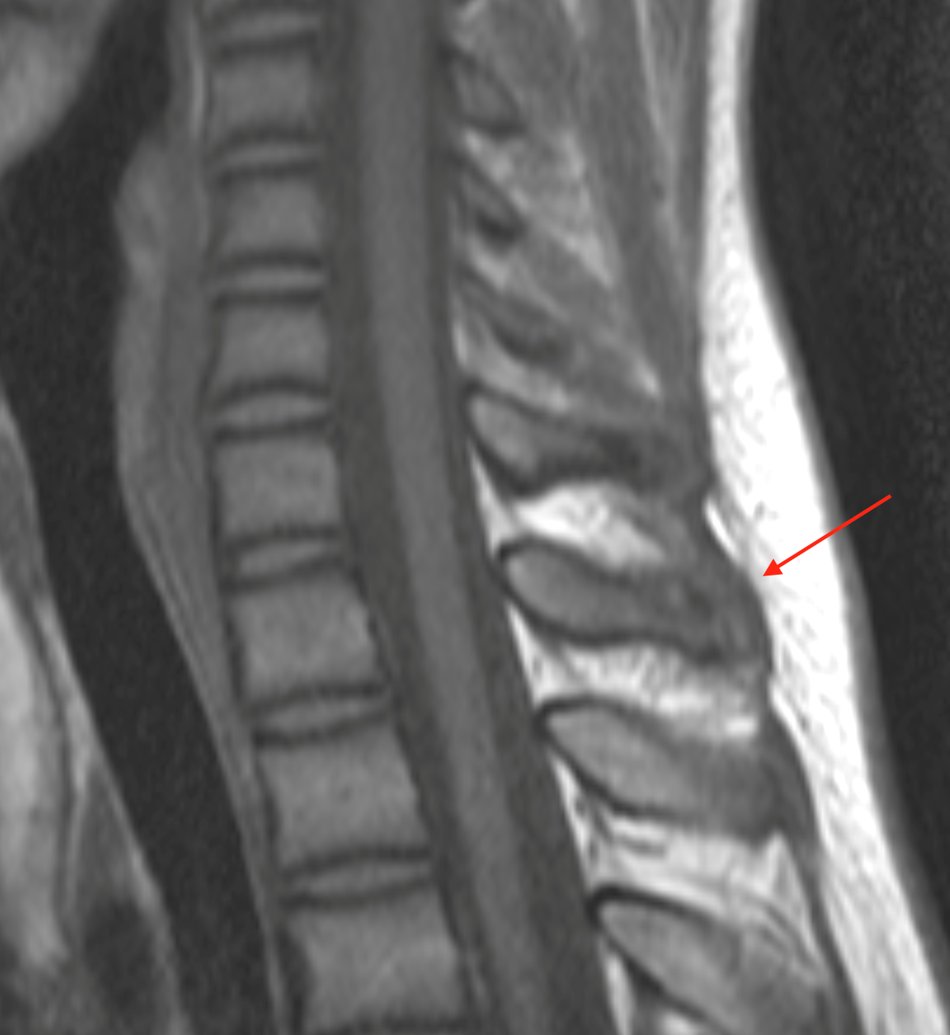

Similar case to yesterday's 🤩this time apophyseal injury at the level of the transverse process #spineimaging #medtwitter #radres #FOAMrad #radiology

mskteachingroom's tweet image. Similar case to yesterday's 🤩this time apophyseal injury at the level of the transverse process